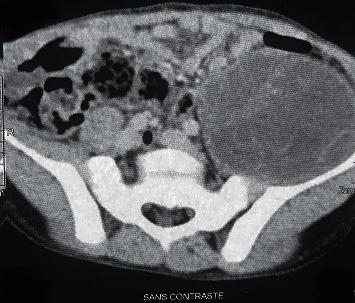

The child was consulted for painless and afebrile lameness of the left hip evolving since 3 months. The clinical examination finds a mass of the left flank. Investigations based on the abdominal ultrasound in first intention showed a hydatid cyst depending on the left psoas muscle. Pelvic CT and abdominal MRI were able to confirm the diagnosis and allowed a better study of the cyst neighboring elements. The drainage of the cyst followed by pericystectomy after evacuation of the vesicles contained in the cyst was done as radical treatment.

该患儿因左侧髋关节无痛性、无发热性跛行3个月前来就诊。临床检查发现左侧腰腹部有一肿块。初步的腹部超声检查显示一个依附于左侧腰大肌的包虫囊肿。盆腔CT和腹部MRI能够确诊,并有助于更好地研究囊肿周围的组织。在排空囊肿内的囊泡后,进行囊肿引流及囊肿切除术作为根治性治疗。